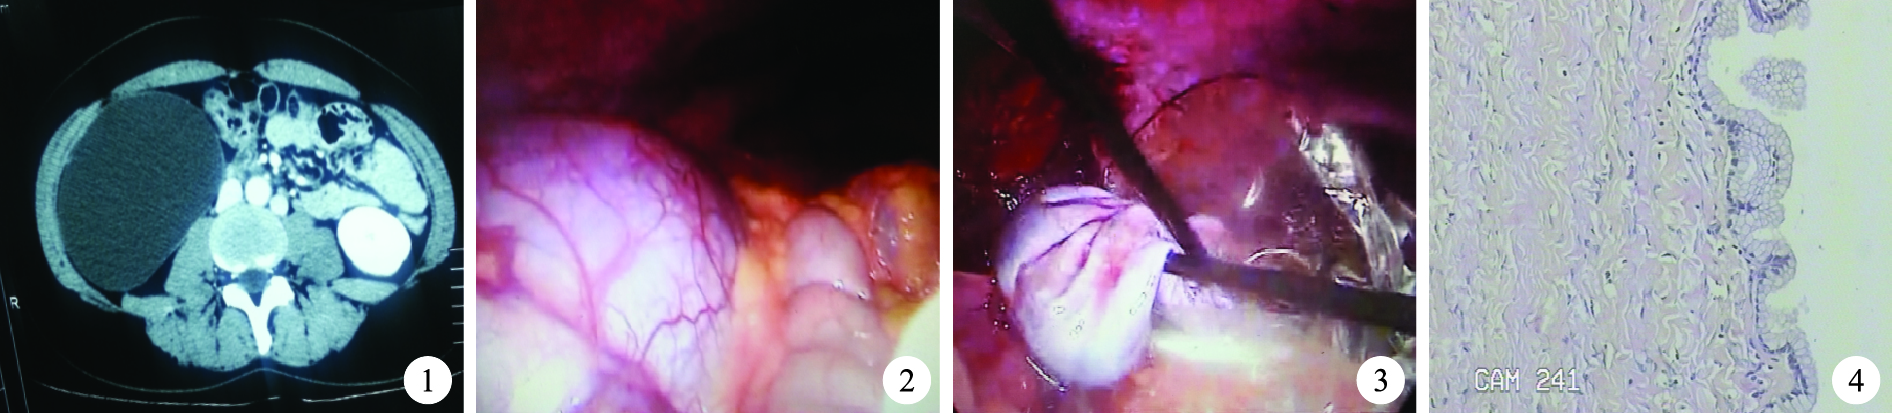

病例資料 患者,女,33歲,因“發現右腹部腫塊伴疼痛1個月”入院。入院時患者無腹脹、腹痛、惡心、嘔吐及發熱,體質量無變化,二便正常。查體:右中上腹觸及一約20 cm×15 cm大腫塊,質韌,無活動,輕壓痛。腹部彩超檢查示:右上腹見巨大低回聲腫塊(23 cm×19 cm×15 cm大),邊界清。腹部增強CT檢查示(圖 1):右上腹巨大囊性低密度灶(20 cm×18 cm×15 cm大),密度均勻,增強未見強化,平均CT值為2 HU,與周圍鄰近臟器及組織未見明顯粘連。以“右腹膜后囊腫”行腹腔鏡手術。術中見腫塊巨大(圖 2),約25 cm×20 cm×20 cm大,位于右上腹膜后,表面光滑,囊性,囊壁薄,質軟,與周圍組織輕度粘連,升結腸被巨大腫物推向內側。于腹腔鏡下分離粘連,完整切除腫物,以穿刺針吸出囊液,見囊液清亮、呈淡黃色;腫塊包膜完整、血管少、未累及重要血管。用標本采集器將標本取出(圖 3)。術后腫塊病理學檢查示:良性囊腫,內襯單層扁平上皮及立方上皮(圖 4)。細胞學檢查示囊液未見惡性腫瘤細胞。術后該患者無并發癥發生,術后5 d痊愈出院,隨訪5個月,期間無腹部不適。